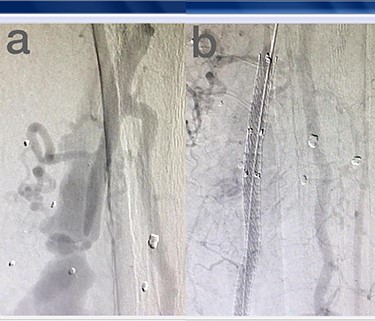

Sites of injury included 6 Posterior Tibialis arteries (27.2%) (Fig. 1), 2 deep femoral arteries (9.09%), 2 Superficial femoral arteries (9.09%) and 2 maxillary arteries (9.09%). We had only one injured artery (4.54%) in each of the following sites: internal pudendal a., Axillary a. (Fig. 2), Proneal a., Lumbar a., External carotid a., Anterior Tibialis a., common iliac a. (Fig. 3), temporal a., Thoracic aorta and Internal iliac artery (Fig. 4).

(a) Branch of Axillary artery before intervention, (b) after coil embolization.